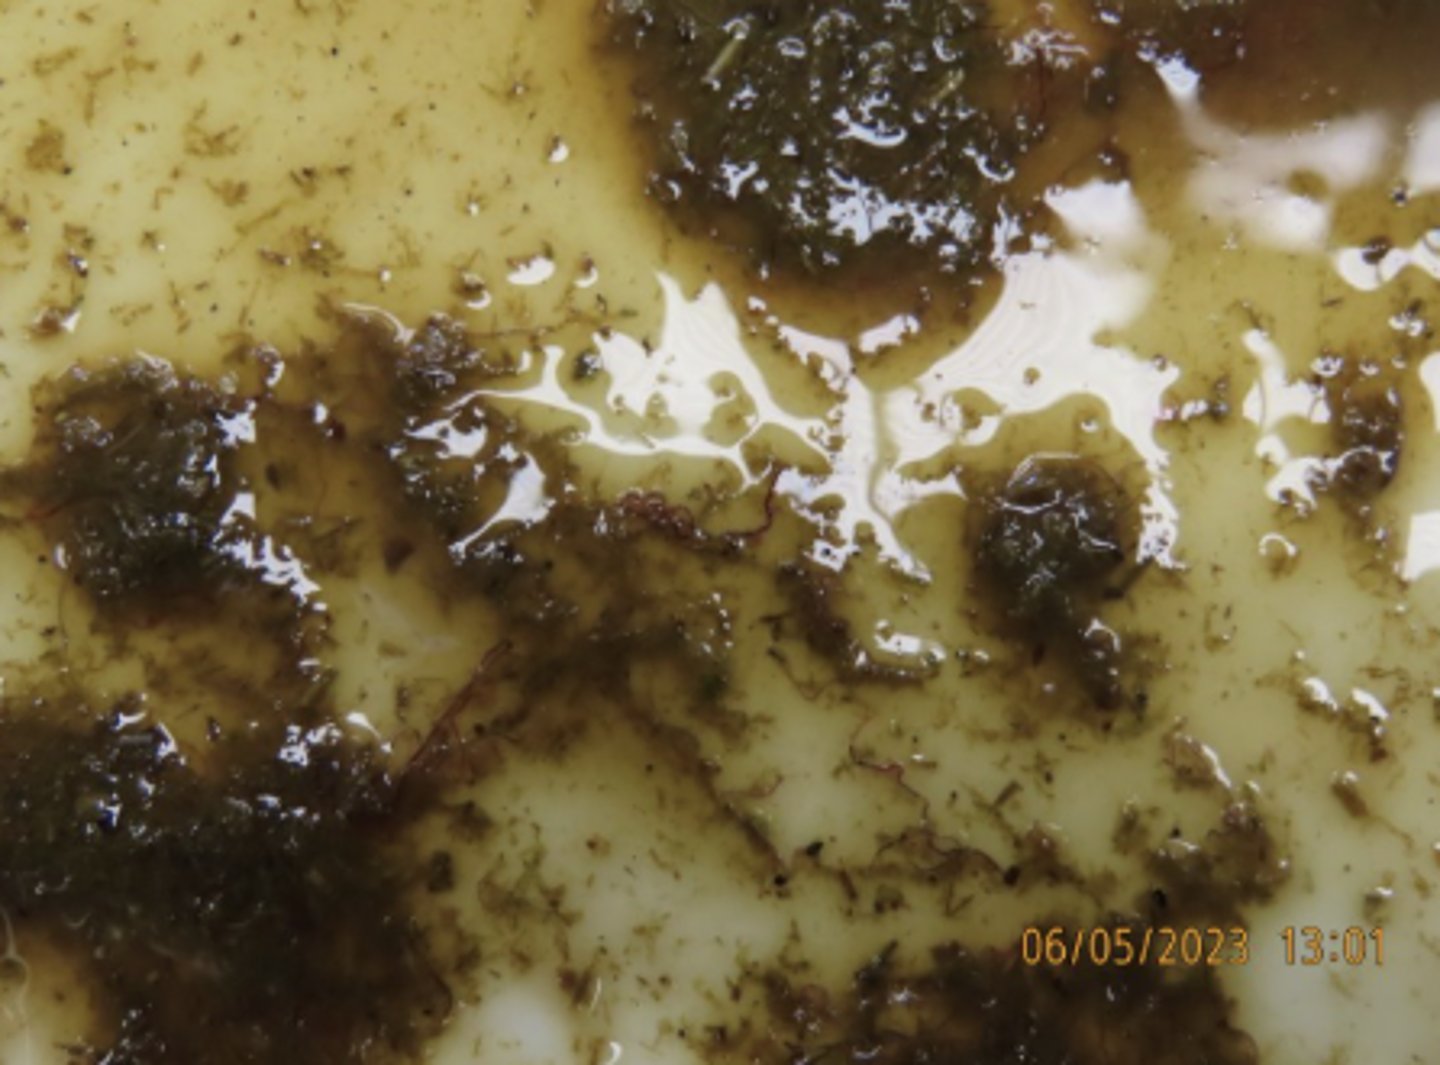

severe verminous abomasitis from Haemonchus contortus

Lesions: disseminated, dozens, round/cylindrical nematodes, off white with distinct red barber pole

Describe these abomasal contents from a goat.